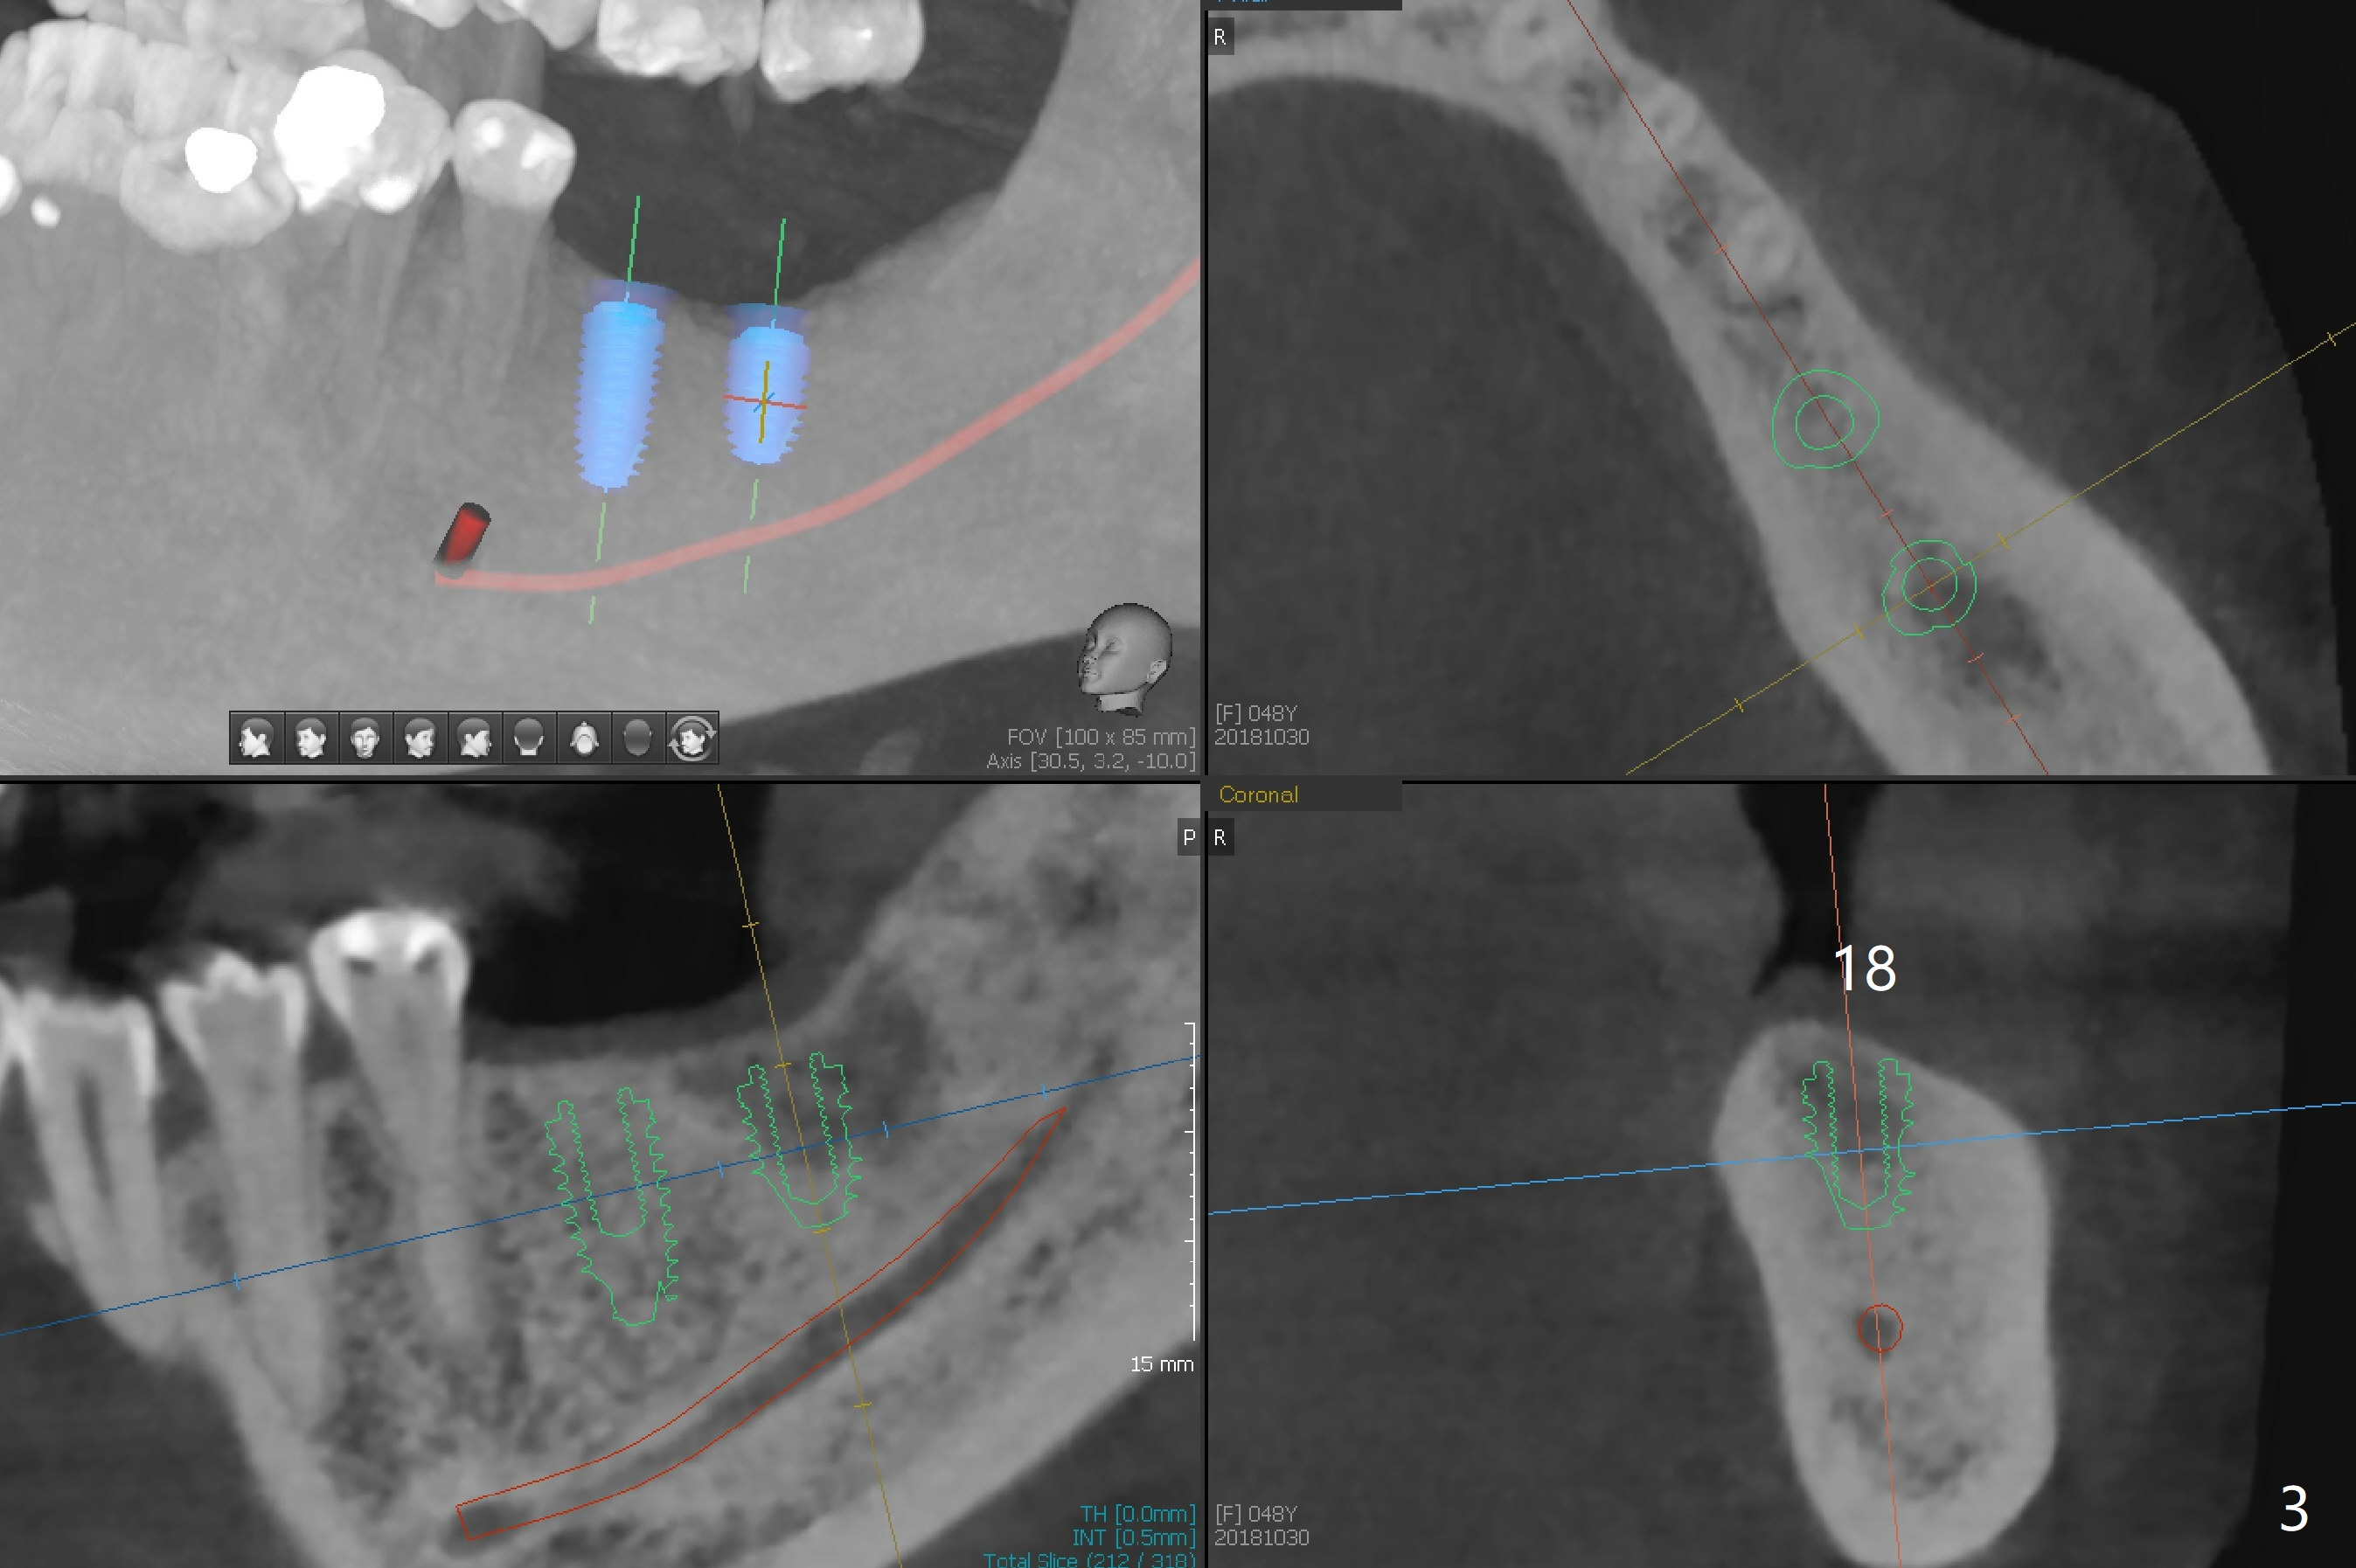

A 48-year-old woman, dentophobic, presents to clinic with request of redo #8,9 composite, which have dislodged twice in the last 6 months. Restoration failure is at least in part due to partial edentulism (#18,19,30, Fig.1). After discussion, she agrees to have implants at #18 and 19 first with guide (Fig.2,3). An ideal treatment plan for #30 (narrow mesiodistal space) would be extraction of #32 (ML fracture), uprighting of #30 and placement of a normal diameter implant. Considering dentophobia and living far from the office, a practical option will be a 3x12 mm 1-piece implant (Fig.4).